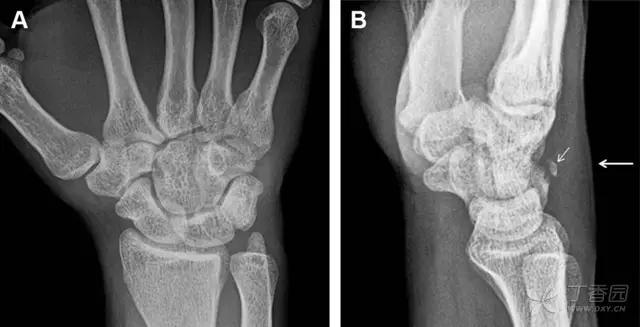

32 掌板骨折

掌板是掌指关节和指间关节关节囊掌侧的纤维结构,防止关节过伸。掌板的远端部是增厚的纤维软骨,附着于指骨掌侧基底部,而其两侧与侧副韧带的纤维融合。掌板骨折多发生于过伸损伤,为撕脱性骨折。

图 3 掌板骨折(A~C)小指前后位、斜位、侧位片,由于骨折的部位及特点,在前后位片上通常难以发现骨折;放大后的斜位(D)、侧位(E)可见一骨碎片(白色箭头)